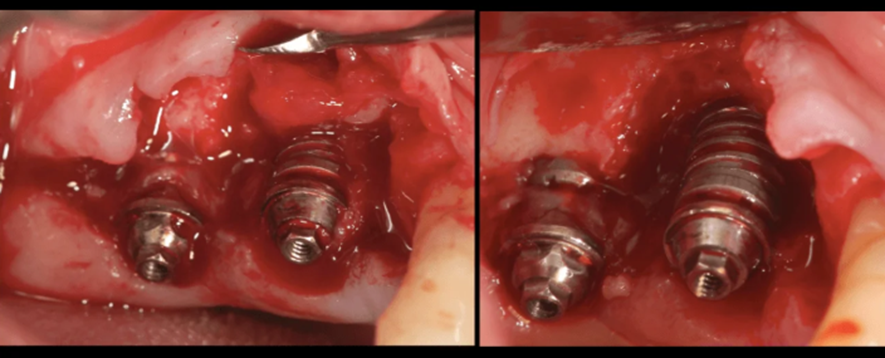

A colocação de implantes tipo Cone Morse em posições muito “rasas”, quase que ao nível da crista óssea ou ligeiramente abaixo dela pode trazer alguns problemas. O principal deles é a falta de espaço interoclusal, o que acaba gerando uma dificuldade na hora da confecção da prótese. Nestas situações os clínicos acabam utilizando pilares muito curtos (com 0,8 mm de altura) o que, segundo alguns artigos da literatura1, pode deflagar uma peri-implantite pela compressão do espaço biológico peri-implantar. A figura 1 ilustra uma situação deste estilo.

Este caso foi solucionado através da realização de uma implantoplastia (remoção e alisamento, com brocas de alta rotação e borrachas de polimento, das espiras contaminadas e que sofreram perdas ósseas). Após dois anos de controle, observou-se que a perda óssea cessou e a saúde peri-implantar foi reestabelecida. As figuras 2 a 4 ilustram a técnica de implantoplastia.